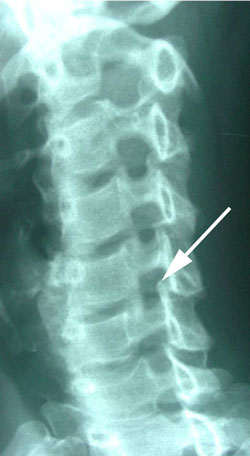

retrolisthesis subluxation

Figure 1 shows the cervical spine, or neck, from a side view. At the arrow notice how the vertebra is moved backward on the vertebra below it. This is called retrolisthesis subluxation and occurs because the intervertebral disc between the vertebrae has been torn and sprained to the point that it can no longer hold the vertebrae in normal alignment. Such malpositioning of the vertebra is a clue to the possibility of a disc herniation and disruption inside of the disc to allow the excessive movement of one vertebra on its adjacent segment. Such movement is termed instability.